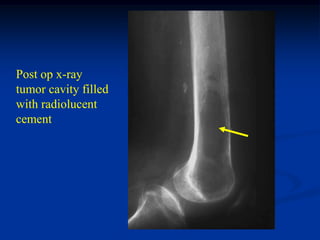

Post op x-ray

tumor cavity filled

with radiolucent

cement